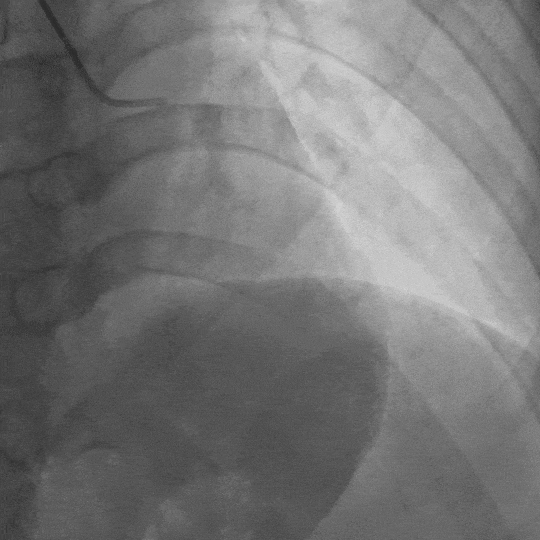

影像素材 | 患者冠状动脉造影3:右冠起源于左冠窦,较细小,开口及近段狭窄不明显,血流TIMI3级

基于这个判断,李医生为张先生安排了更精确的检查——冠状动脉CT造影。结果果然发现了异常:患者的右冠状动脉起源异常且纤细,同时左前降支存在“心肌桥”。

这还不是最终答案。为了看得更清楚,李医生建议张先生住院接受冠状动脉导管造影——这是诊断冠脉问题的“金标准”。